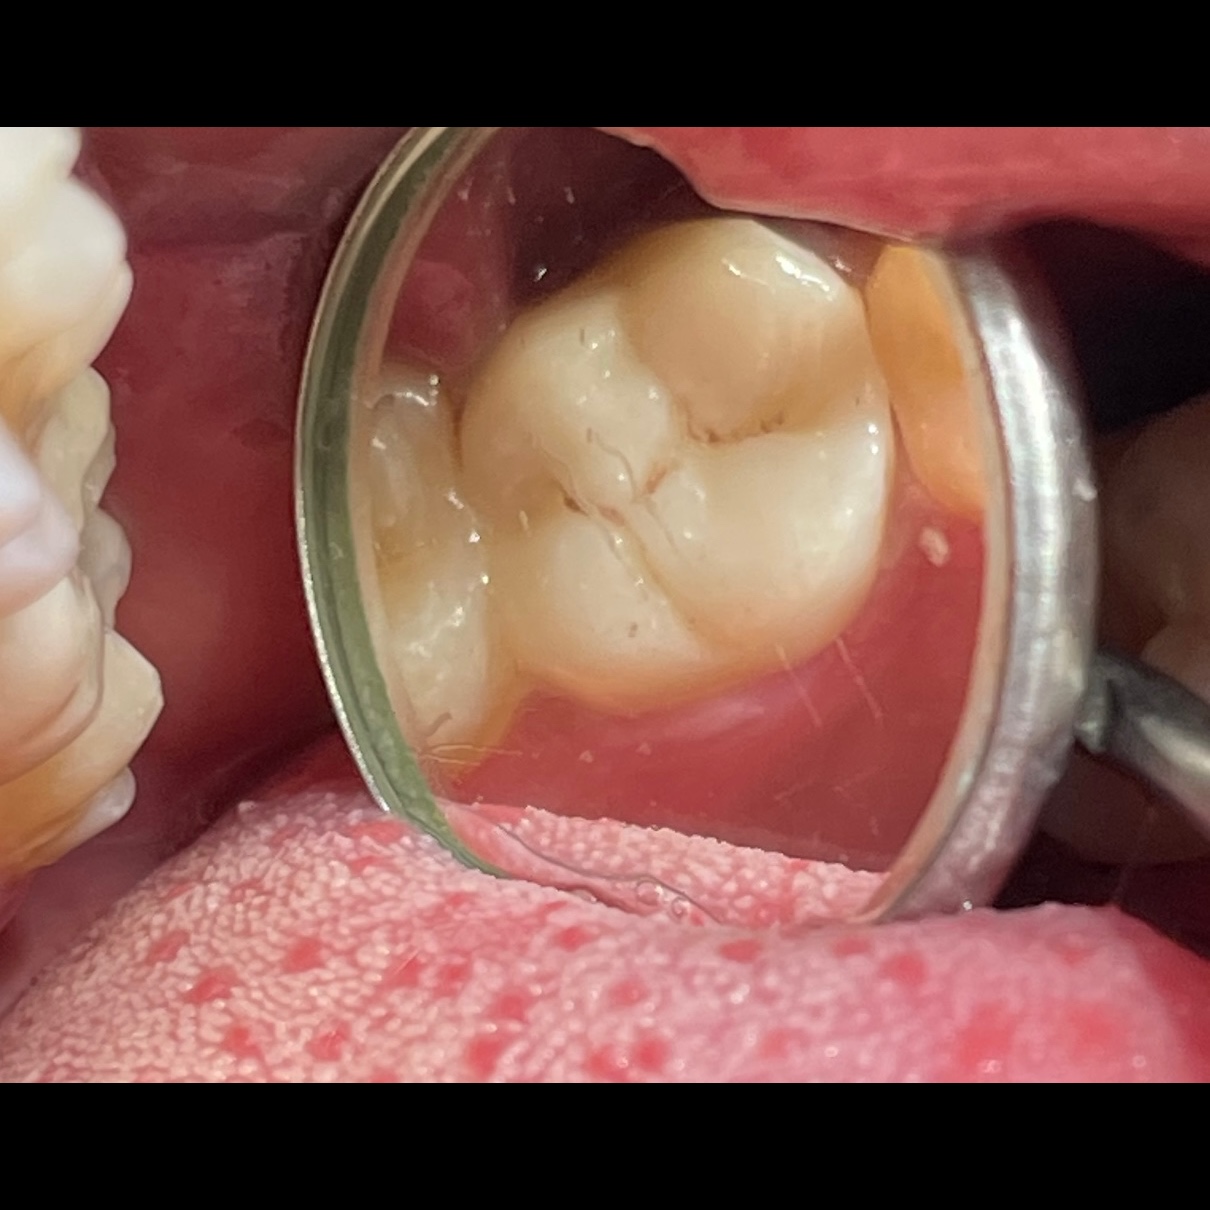

Get your problems solved with DHAANYA’S DENTAL CLINIC at Mogappair! Rheumatoid arthritis (RA) can have implications for dental care and oral health due to its systemic nature and potential effects on the joints, connective tissues, and immune system. Here are some key points related to rheumatoid arthritis and dentistry: 1. Oral Health Issues: Dry mouth (xerostomia) due to medications like methotrexate or Sjögren's syndrome, which can increase the risk of tooth decay and gum disease. 2. Periodontal Disease: tooth loss if untreated. Chronic inflammation associated with RA may exacerbate gum disease, leading to 3. Jaw Joint Problems: TMJ (temporomandibular joint) disorders, jaw pain, difficulty chewing, and clicking or popping sounds in the jaw. 4. Medications: nonsteroidal anti-inflammatory drugs (NSAIDs) and corticosteroids, can affect dental treatment plans, such as potentially increasing bleeding during procedures. -Methotrexate: Can cause oral ulcerations or mucositis as a side effect. Dental treatment may need to be timed to avoid exacerbating these symptoms. -Biologics and Corticosteroids: They suppress the immune system, potentially increasing the risk of infection after dental procedures. Routine dental Care: Regular dental visits are crucial for RA patients to monitor oral health Collaboration with Rheumatologist: Dentists may collaborate with rheumatologists to coordinate care, especially if the patient requires premedication with antibiotics before dental procedures due to compromised immune systems or joint prostheses. 7. Treatment Modifications: During flare-ups of RA, modifications to dental treatment plans may be necessary to accommodate joint pain and stiffness. 8. Patient Education Overall, maintaining good oral hygiene and addressing dental issues promptly is important. Rule of Twos Adrenal suppression may occur if: patient is taking 20 mg of cortisone or its equivalent daily& for 2 weeks within 2 years of dental treatment Steroid cover regimen: Doubling the dose of current regimen on the day of surgery